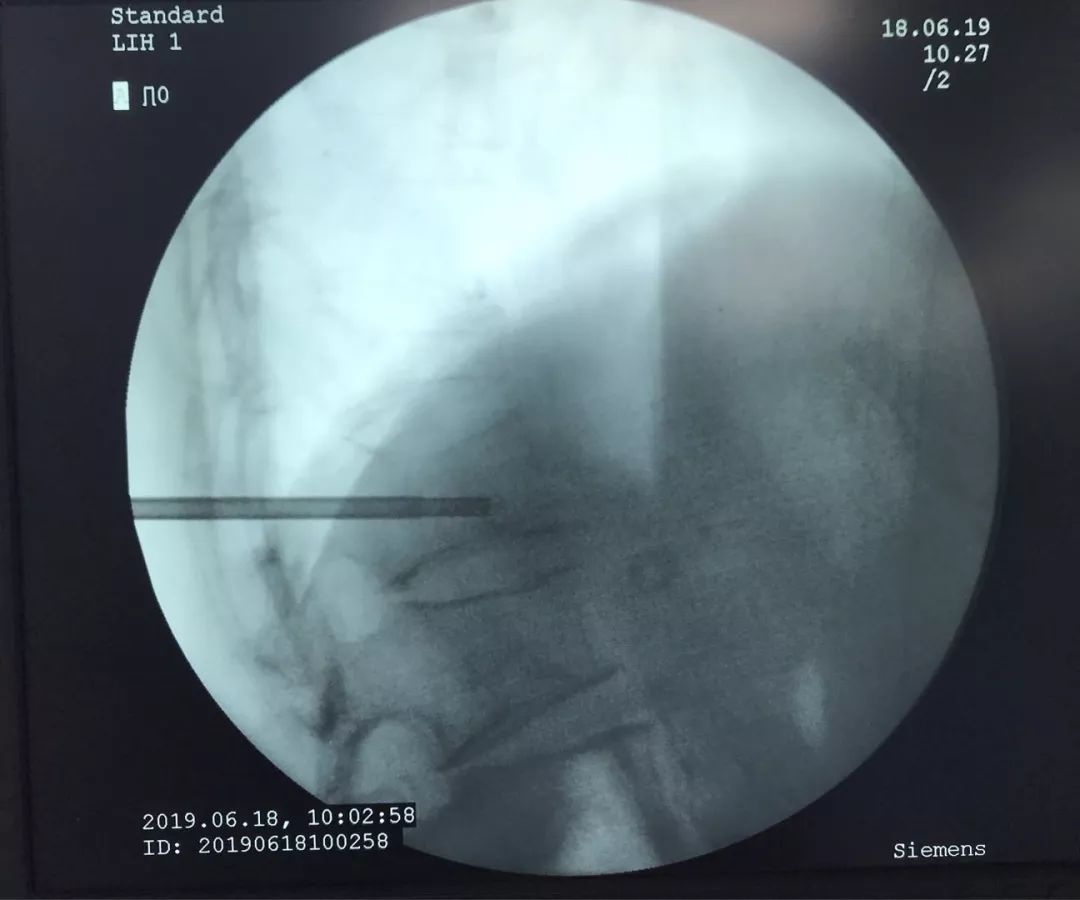

术中椎体穿刺时,椎体密度显著下降,穿刺阻力显著降低,引流暗褐色血性液体,送病理检测。

骨水泥灌注术中